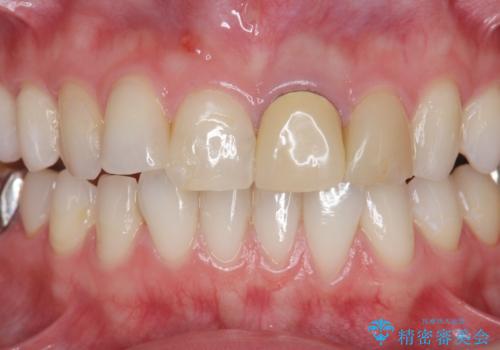

- 長年気になっている前歯の見た目を改善したいと来院されました。

両側の前歯に根尖性歯周炎を認めたため根管治療を行ったのち、ジルコニアクラウンを用いた審美性の改善を計画します。

前歯の見た目が改善したことで長年の悩みが解決できた。と治療内容に満足いただくことができました。